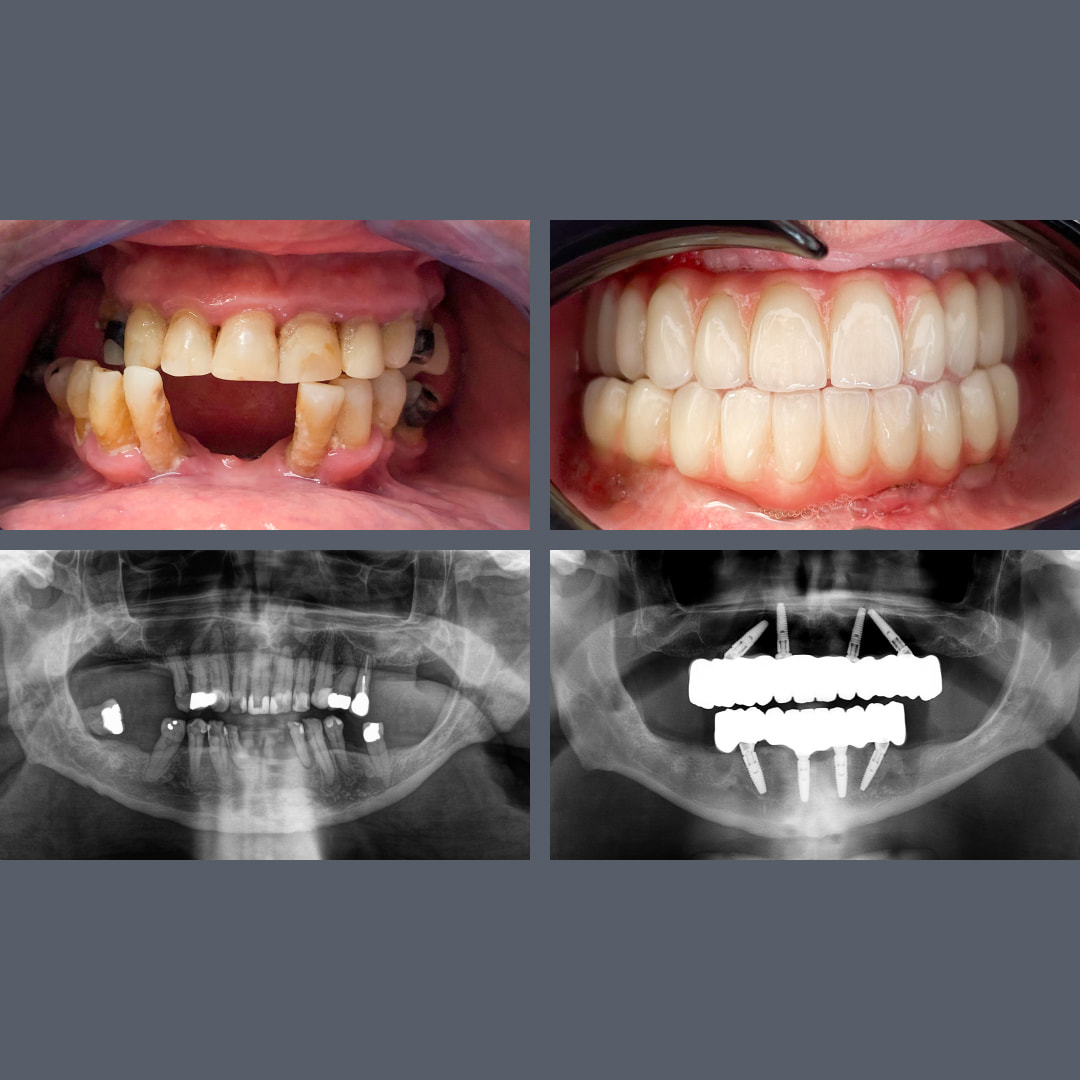

Full-Mouth Restoration: Upper and Lower All-on-4® Solution in Just 7 Months

Treatment: ALL-ON-4®